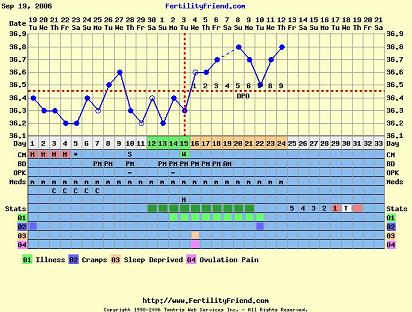

Holnap majd jövök az ideillő görbémmel